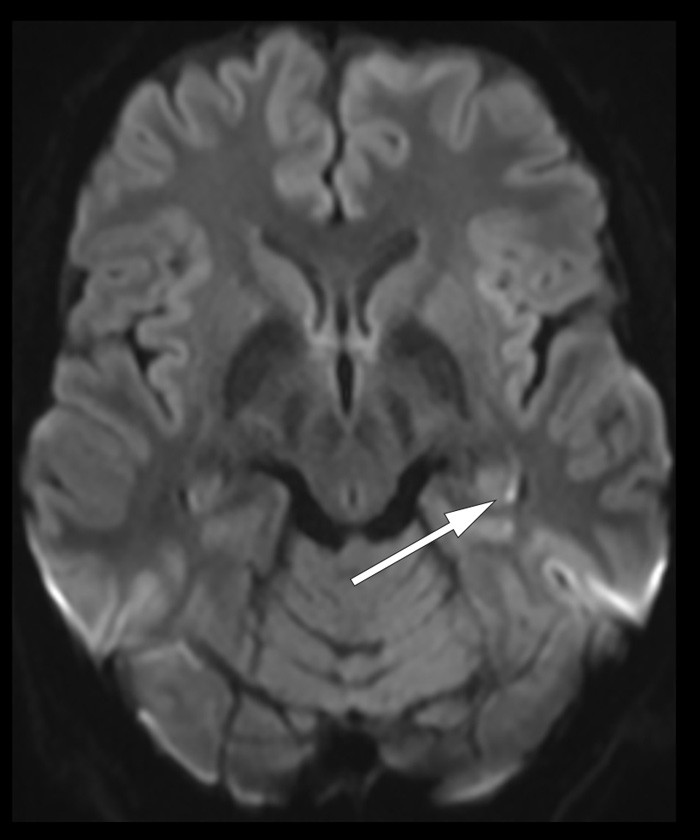

Clinical examination in the accident and emergency department revealed no current neurological deficits, beyond anterograde amnesia, and CT of the head was unremarkable. Further examination two days later showed a normal EEG with no signs of epileptic activity. Diffusion-weighted MRI of the brain revealed a 2 mm wide diffusion lesion in the left caudal hippocampus (arrow). Such subtle diffusion abnormalities in the hippocampus are typical of transient global amnesia (TGA) (1).